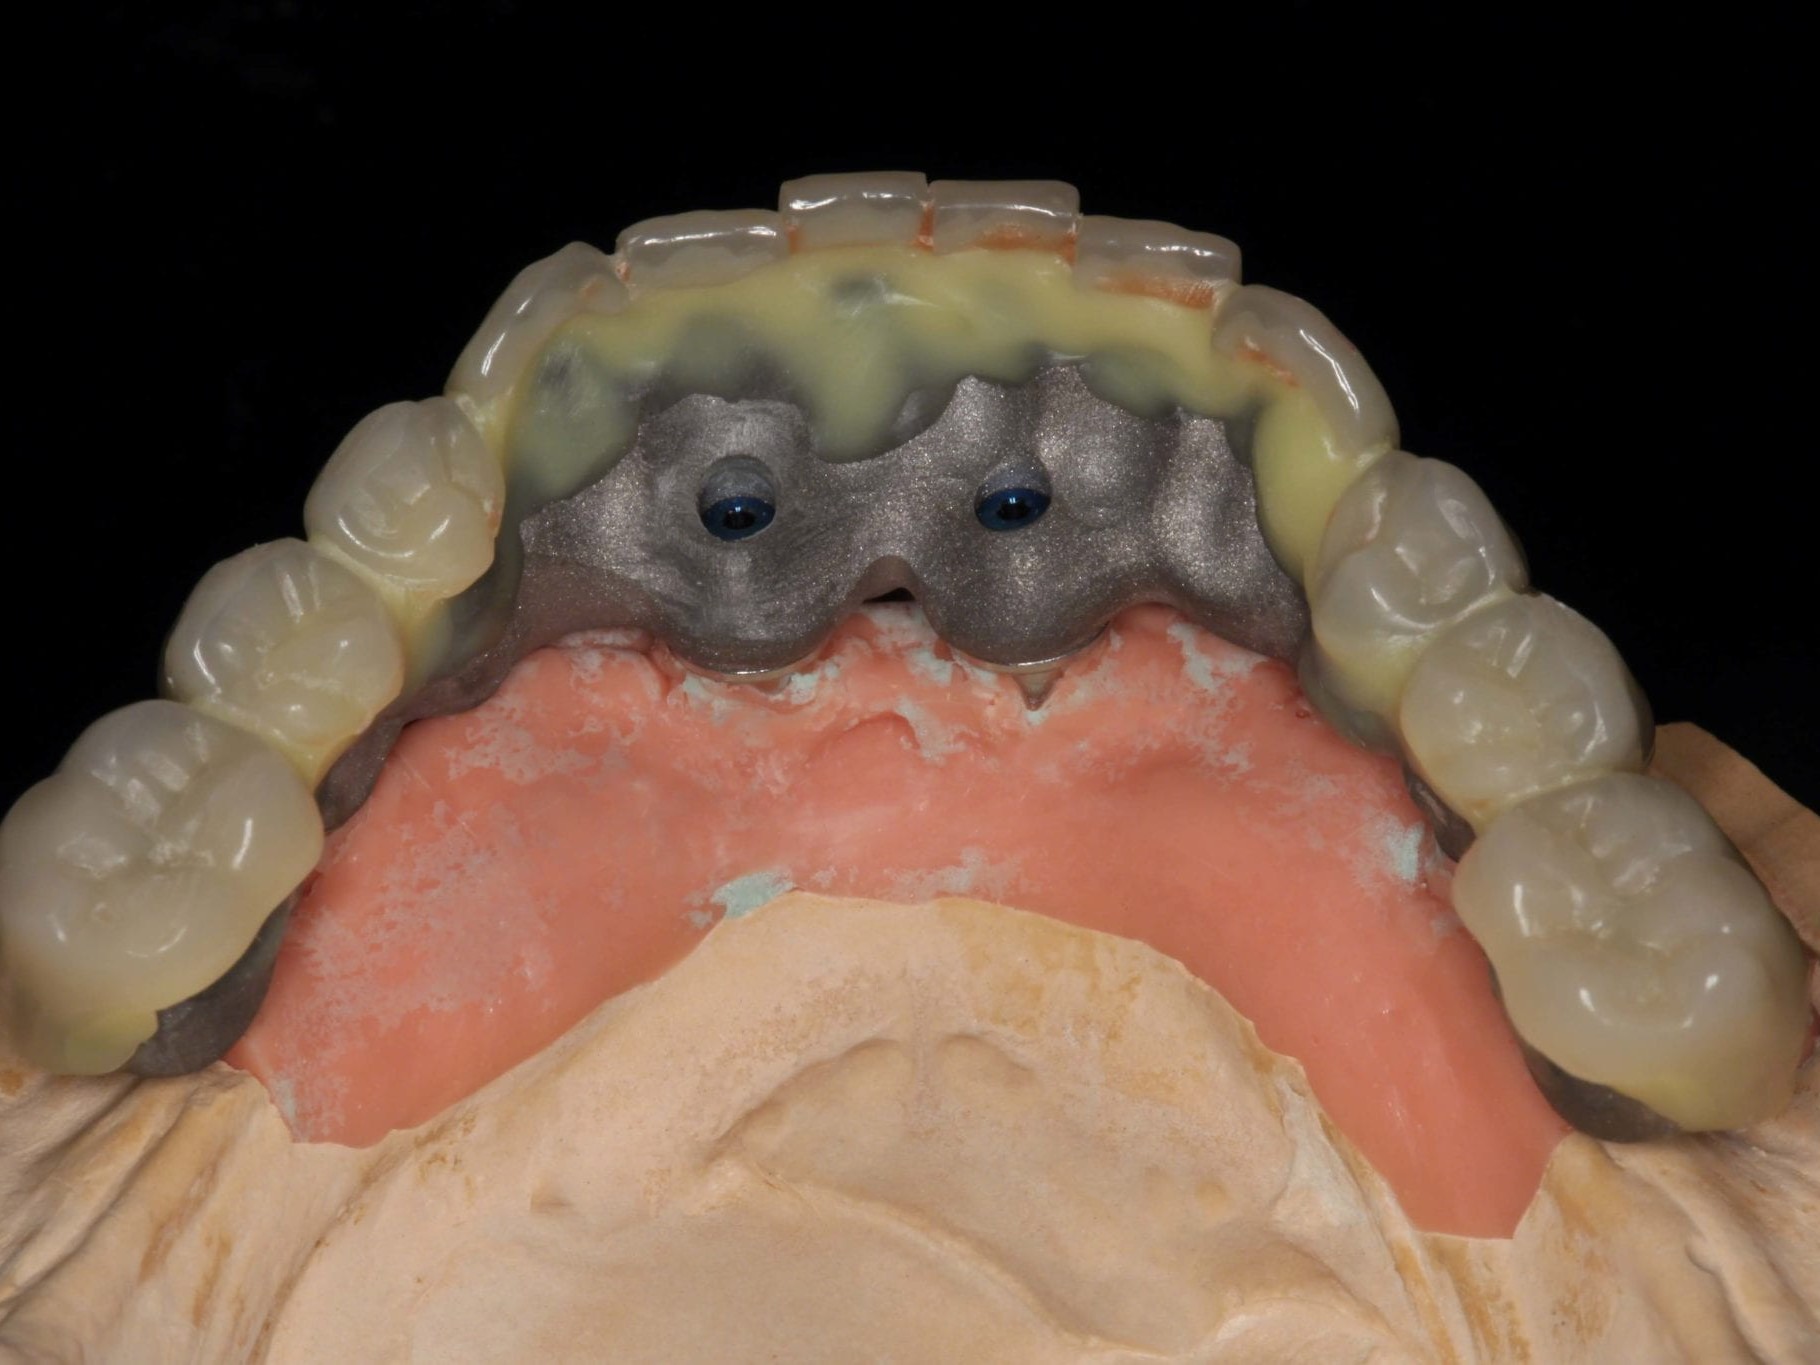

Der gesamte Workflow dieses Patientenfalles beruht auf dem Prinzip des Backward Planning. Sowohl bei der Chirurgie als auch bei der Prothetik ist dem Team aus implantatchirurgischen und implantatprothetischen Behandler und Zahntechniker daran gelegen, vorhersagbare Ergebnisse zu garantieren. Bei einer okklusal verschraubten Brücke ist es für den Zahntechniker vor Beginn der Arbeit wichtig, den späteren Austrittspunkt der Schraubenkanäle zu kennen und eine diagnostische Aufstellung in Form und Funktion anzufertigen. Nur so wird gewährleistet, dass das CAD/CAM gefertigte Gerüst optimal die Verblendungen unterstützt und die Schraubenkanäle ideale Durchtrittspunkte bekommen. Nach der Anfertigung der Aufstellung im Labor wurde der Patientenfall im ATLANTIS WebOrder Portal von Dentsply Implants angelegt und das Meistermodell mit der diagnostischen Aufstellung an die ATLANTIS ISUS Produktion nach Belgien geschickt. Die Durchführung und Digitalisierung des Meistermodells und die Erarbeitung eines Designvorschlages für das anatomisch reduzierte Brückengerüst erfolgte unter Verwendung einer speziellen CAD–Software. Obwohl der Designprozess in diesem Schritt zumindest nicht direkt in den Händen des Zahntechnikers liegt, bedeutet es aus Sicht der Autoren nicht den Verlust von Kompetenz oder Designfreiheit. Auch hier gilt: Bevor eine Arbeit in die zentrale Fertigung geht, benötigt sie die Freigabe durch den Zahntechniker. Das ATLANTIS ISUS Team geht auf die Änderungswünsche des Zahntechnikers ein und unterbreitet weitere Designvorschläge, bis ein Vorschlag perfekt ist und akzeptiert wird. Die auf den zehntel Millimeter genau festzulegende Reduktion des Gerüstes (Abb. 3) richtet sich nach der Indikation der Verblendung.

Wie weiter oben bereits beschrieben ist die Patientin im Oberkiefer mit einer keramisch verblendeten implantatgetragenen Brücke versorgt. Aus Sicht des Behandlungsteams schied daher eine keramische Verblendung des Unterkiefers aus. Die Verwendung von einem Composite mit keramischer Füllstruktur gewährleistet neben der notwendigen Farbstabilität und Plaqueresistenz zwei weitere Vorteile. Auf der einen Seite entsteht im Okklusionsmoment nicht das „keramische Klacken“ und zum anderen werden die auftretenden Kaukräfte gleichmäßiger auf das Implantat und den Knochen verteilt . Gerade bei implantologischen Oberkiefer- und Unterkieferversorgungen ist dieser „Stoßdämpfer–Effekt“ für den Langzeiterfolg wichtig. In dem vorliegenden Fall wurde die okklusal verschraubte Brücke aus einem massiven Titanblock gefräst (Abb. 4 und 5), wodurch das Endprodukt frei von aus der Gusstechnik bekannten Lunkern oder Verzügen ist. In Übereinstimmung mit den als Sheffield-Test ⁷ bekannten Kriterien der University of Sheffield, GB. ermöglicht dieser Fertigungsprozess gepaart mit der verblockten Abdrucknahme einen präzisen und somit spannungsfreien Sitz der Brücke – sowohl auf dem Meistermodell als auch im Munde des Patienten. Sowohl die Verblendungen der Zähne als auch des Zahnfleisches wurden unter Zuhilfenahme der diagnostischen Aufstellung mit visio.lign ⁸ im Labor angefertigt. Hierbei wurde besonderer Wert auf die naturgetreue Nachbildung der Rot-Weiß-Ästhetik und eine gute Hygienefähigkeit gelegt. Die Vorteile dieses Verblendsystems liegen in der exakten Umsetzung von der Aufstellung hin zur fertigen Arbeit durch mehrschichtige Verblendschalen (Abb. 6). Diese Verblendschalen werden schon bei der diagnostischen Aufstellung individualisiert und nach der Gerüstfertigstellung weiterverarbeitet. Mit passenden Individualisierungs- und Ergänzungsmassen sowie einem farblich abgestimmten Verbundsystem mit sehr guter Druck-Scheer-Festigkeit ⁹ ermöglicht dieses System durch Hinterlegen mit Intensivfarben das Gestalten von Mamelons ebenso wie die individuelle Gestaltung von Dentinleisten. (Abb. 7 und 8). Nach der zahntechnischen Erstellung der Unterkieferbrücke wurde diese intraoral inkorporiert (Abb. 9a). Die Implantatschrauben wurden mit 25 Ncm angezogen. Ein wichtiger Hinweis ist, dass hier stets das Originalequipment des Herstellers oder ein elektronisch kalibrierter Schraubendreher seine Anwendung finden sollte. Die Schraubenkamine wurden initial mit einem bakteriendichten, formstabilen lichthärtenden temporären Füllungsmaterial ¹⁰ verschlossen (Abb. 9b). Nach 6 Wochen werden die Implantatschrauben seitens des Prothetikers nochmals kontrolliert und ein abschließendes OPG erstellt (Abb. 10).